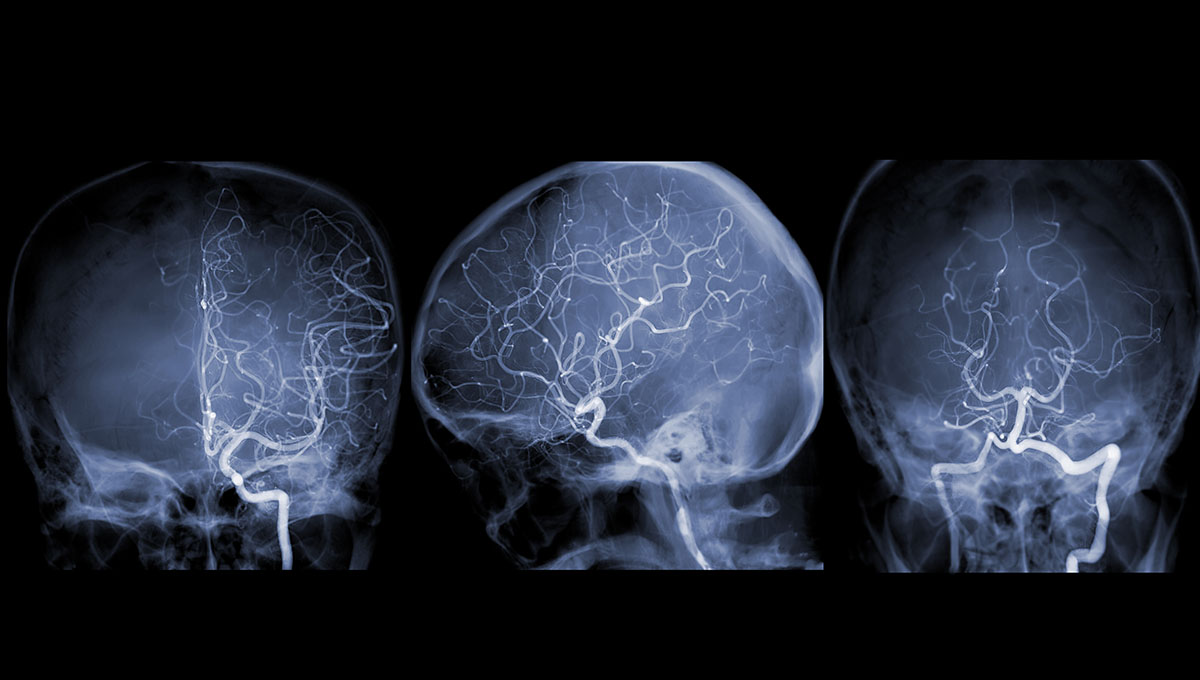

Efficacy and safety of a new mechanical balloon-based flow diverter in the treatment of intracranial aneurysms  jnis.bmj.com May 8, 2026, 10:40 p.m.

The mechanical balloon-based FD showed a remarkable occlusion rate alongside minimal ischemic and hemorrhagic adverse events compared with existing FDs. This innovative mechanical balloon-based design may be an important direction for future FD design.

Early Flow-Diverter Implantation in Ruptured Intracranial Aneurysms: Safety and Outcomes in a Resource-Limited Setting neurointervention.org March 16, 2026, 9:56 a.m.

Early FD implantation in carefully selected ruptured aneurysms, including small saccular and morphologically complex lesions can achieve high functional recovery and complete angiographic occlusion, even in a resource-limited environment. Ideal case selection and standardized DAPT and hemodynamic protocols are critical. These findings support broader use in challenging aneurysms, but larger prospective studies are warranted to validate outcomes and refine management strategies.

Early Flow-Diverter Implantation in Ruptured Intracranial Aneurysms: Safety and Outcomes in a Resource-Limited Setting neurointervention.org March 11, 2026, 3:08 p.m.